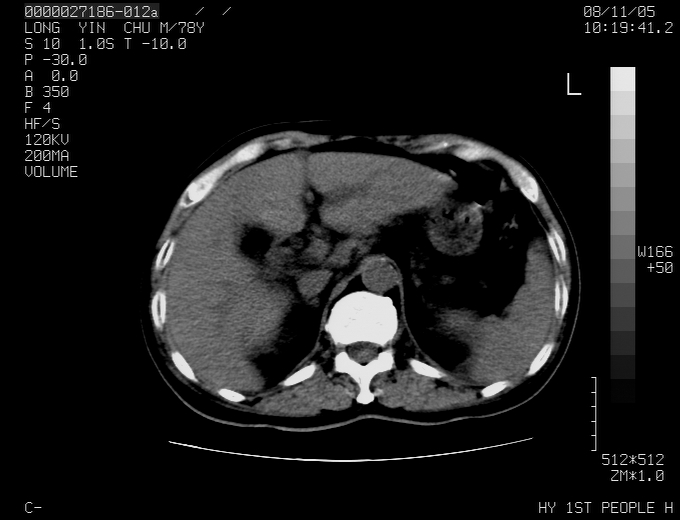

标题: CT16532:M78Y,肝脏病变,请会诊

腹胀,腹痛就诊,男性,78岁,外院b超未见异常。

肝ca,脾肾转移

考虑弥漫性肝癌并脾及双肾转移.双侧胸水.

考虑弥漫性肝癌并脾及双肾转移.双侧胸水.  支持

考虑弥漫性肝癌并脾及双肾转移,双侧胸水。